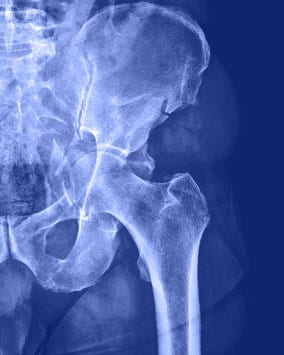

Alle Erkrankungen und Komplikationen, die abhängig vom Muskel- und Skelettsystem auftreten, sind mit den Geräten auf dem neuesten Stand der modernen Medizin und Fachchirurgen zu behandeln. Die Traumen, die die abhängig von den Unfällen und Verletzungen auftreten, sind mittels der günstigsten chirurgischen Techniken einzugreifen. Alle Gelenk-, Muskel-, Knochen-, Nerven-, Gefäß- und Wirbelsäulenprobleme gehören zur Orthopädie. Die Station für Orthopädie und Traumatologie bietet die Behandlungsdienste, die organisiert mit der Station für physikalische Therapie und Rehabilitation zu erbringen sind.